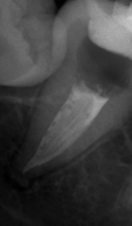

В стоматологической клинике "5 Принципов" в Симферополе мы гордимся тем, что каждый пациент получает индивидуальный подход и безупречный результат в области эндодонтического лечения под микроскопом. Наши специалисты применяют современные цифровые технологии, микропроцессорные и нейромодуляционные инструменты, что позволяет достичь максимальной точности и минимального дискомфорта. В портфолио клиники — широкий спектр кейсов: от первичной диагностики пульпита до сложной ретенированной резорбции и повторной эндодонтии. Мы беремся за зубы любых степеней сложности: от моляра до резцов, используя щадящие концевые инструменты и безболезненные методы постоянной анестезии. Все процедуры проходят под увеличением, что обеспечивает точное удаление инфицированной ткани и сохранение естественной анатомии зуба.Особое внимание мы уделяем постпроцедурному наблюдению: контроль за герметичностью заполнения корневых каналов, профилактические рекомендации и возможная корректировка плана лечения при необходимости. В "5 Принципах" мы разумно сочетаем комфорт, эстетическую привлекательность и долгосрочную функциональность. Результат — здоровые зубы, уверенная улыбка и спокойствие наших пациентов в Симферополе. Запишитесь на консультацию и убедитесь сами в нашем подходе к качественному эндодонтическому лечению.